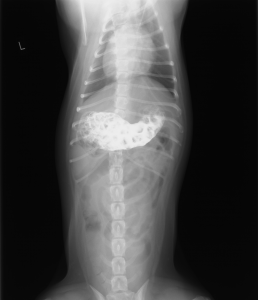

レントゲン検査をしてみると、胃内に何か物が認められます。これが吐気の原因のようです。

こちらは、造影剤投与後のレントゲン写真です(この時点では、胃内異物が何であるか判明しませんでした。)

この後、時間をあけて再度撮影しましたが、胃の内容物は全く移動しませんでした。胃停滞が生じているようです。

それにともない、腸内のガス貯留像が増えてきました。あまり良い所見ではありません。